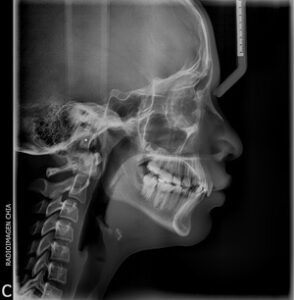

La telerradiografía Lateral Digital es una radiografía en la que se evalúa el perfil del paciente, sus tejidos blandos y óseos, es habitual en estudios y control de tratamientos de ortondoncia, patologías craneomandibulocervicales y cirugía ortognática y plástica, entre otros.